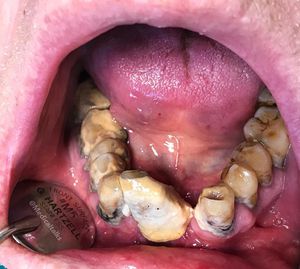

He came to clinic for teeth pain due to periodontitis. The examination revealed existence of deposits on the teeth, known as calculus. In dentistry, calculus or tartar is a form of hardened dental plaque. It is caused by precipitation of minerals from saliva and gingival crevicular fluid in plaque on the teeth. This process of precipitation kills the bacterial cells within dental plaque, but the rough and hardened surface that is formed provides an ideal surface for further plaque formation. This leads to calculus buildup, which compromises the health of the gingiva (gums). Calculus can form both along the gumline, where it is referred to as supragingival, and within the narrow sulcus that exists between the teeth and the gingiva, where it is referred to as subgingival. Calculus formation is associated with a number of clinical manifestations, including bad breath, receding gums and chronically inflamed gingiva. Brushing and flossing can remove plaque from which calculus forms; however, once formed, it is too hard to be removed with a toothbrush. Therapy included removal of deposits and multiple tooth extraction with dental prosthesis implantation. Photo by @dr_stanic